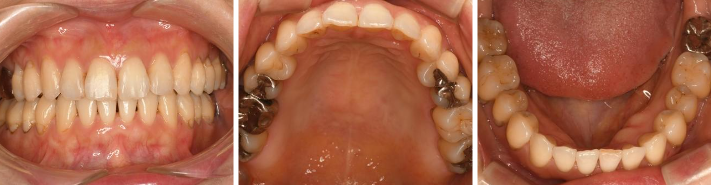

そして7ヶ月半の術後はこちら

短期間で歯のがたつきが改善されました

この症例では、歯を抜いたりせず、IPR(主に歯と歯の間を削る処置)をおこなっております